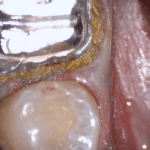

In this clinical video we demonstrate how to scan a molar preparation for the replacement of a crown with recurrent decay and open margins. The molar was root canal treated and the tissue was inflamed. the preparation was imaged and a temporary was fabricated to allow the tissue to heal properly.

The main point of this video is to show how to capture the contacts of the adjacent teeth and the deep marings